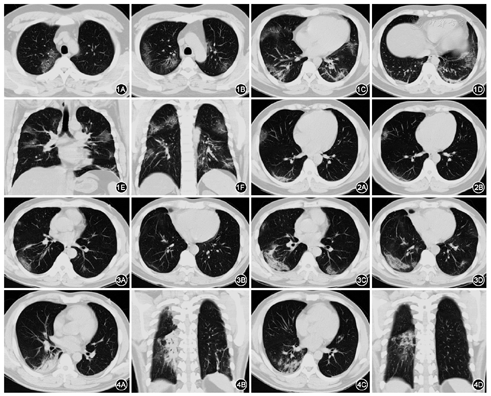

22例2019-nCoV感染治疗后短期(3~5 d)进行复查,21例复查1次,1例复查2次。病变增多10例,病变变化不明显6例,病变减少6例(图1,图2,图3,图4)。

2019-nCoV感染发生于冬春季,多以发热、咳嗽为首发症状。本组中出现发热者30例,咳嗽者23例。本组出现COVID-19 30例,在病毒检测结果未出来之前,肺部炎症的影像表现比发热、咳嗽等更具有提示意义,所有患者进行了平扫CT检查,并进行了后重建拆薄、多平面重组,无增强CT检查。COVID-19的CT影像为病变呈多部位分布,本组累及双肺者29例,胸膜下区或外中带见病变30例,这与何悦明等[7]研究保持一致。其原因可能与胸膜下区为气道末端分布,近距离飞沫传播,病毒颗粒很细,易沉积于细支气管和肺泡部位,也可能与本组病例重症较少有关。SARS、甲型H1N1流感、人感染H7N9禽流感多位于两肺下叶[8,9,10],而本组双肺各叶之间分布差异无统计学意义,其原因也可能与病变发生发展时期有关,部分患者是在其他医院初诊,发现病变后进入本院定点隔离治疗。本组表现为均匀或不均匀磨玻璃密度影25例,实变影共存16例,与SARS、甲型H1N1流感、人感染H7N9禽流感表现相似。磨玻璃密度影见于多种疾病的早期表现,如过敏性肺炎、病毒感染、支原体感染等[11]。早期均匀磨玻璃密度影主要为不同程度的肺泡损伤,肺泡壁有透明膜形成,而肺泡内渗出和水肿并不明显[12]。随着病程进展,逐渐出现不均匀磨玻璃密度影及实变,边界逐渐清晰,呈不规则楔片状或类扇形改变,部分容积减小,其病理改变由单纯肺实质受累进展为肺实质和肺间质同时受损[13,14],可能发生了早期纤维化。间质性改变主要表现为"铺路石征"或索条状及小叶间隔增厚,本组小叶间隔增厚18例,可能与病变累及淋巴道或间质性肺水肿有关。本组胸膜增厚24例,可能与病变早期发生于胸膜下引起病灶邻近胸膜反应有关,本组病例无胸腔积液。只有1例出现纵隔淋巴结肿大,经治疗后有缩小。本组病例中未见小叶中心结节。以上这些影像征象具有一定的特征性,从影像上能够提示COVID-19的早期诊断。

甲型H1N1流感肺炎可见支气管周围和小叶中心的磨玻璃影或实变[15],与本组COVID-19的胸膜下和外周分布较多有所不同。SARS及人禽流感肺炎都具有病情发展快、变化快的特点,CT检查是最直接快速的检查方法,可以快速明确诊断及掌握患者的病情变化以指导临床更新治疗方案。通过病变分布占相对应肺叶面积进行轻、中、重度的判断并进行影像评分,本组10例发现病变有进展,其中2例临床结合影像变化判断有重症倾向,2 d后进展为重症。其中1例重症患者影像评分由12分逐渐降为11、6分,随后该患者解除重症。另外有1例短期复查,右肺下叶网织片状病灶有吸收,由中度转为轻度,该患者符合出院标准遂出院。因此,我们认为此研究方法比单纯统计所占肺野的数量进行轻、中、重度的判断的方法更具有临床价值[16],有利于对病情进行监测及出院判断。